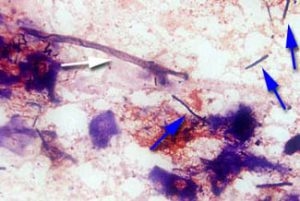

7 main causes of erosions in gizzard and proventriculus - Image 3

Macrorhabdus ornithogaster, picture obtained here.

• Megabacteria (Macrorhabdus ornithogaster), an organism that looks like bacterium but is actually closer to yeast. Originally it was thought to infect ornamental birds only, but it has been shown that they can infect broilers, laying and breeding hens, turkeys, quail and ostriches. At necropsy, the proventriculus is dilated, pale in color, with irregularly shaped glands and sometimes small bruises. Diagnosis in the laboratory: Giemsa stain reveals very large rod-shaped organisms.